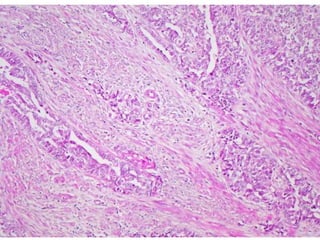

Adenocarcinoma endometrioide

do endométrio